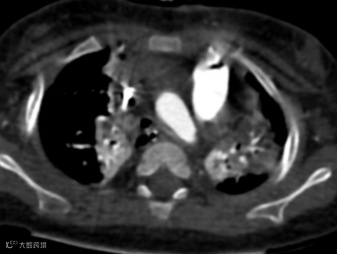

胸部CT增强图像如下:

左肺动脉起源异常,由右肺动脉发出,在气管隆突上方与食管之间形成不完整的环状结构。双肺散在分布多发实变影。

左肺动脉吊带,伴双肺感染